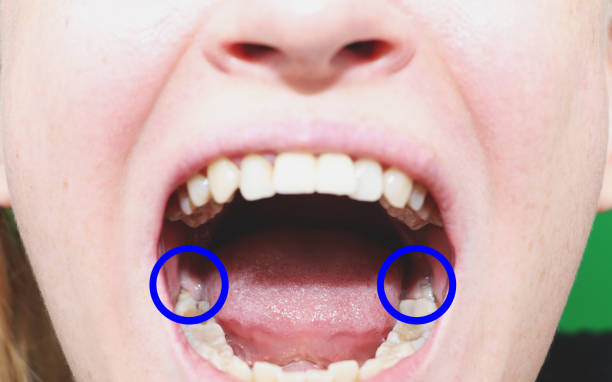

ฟันคุดคือ ฟันกรามซี่ในสุด ทั้งหมด 4 ซี่ บน ล่าง ซ้าย ขวา ไม่สามารถขึ้นได้ตามปกติเพราะพื้นที่ไม่เพียงพอให้ฟันสามารถขึ้นมาได้ บางซี่อาจจะโผล่ขึ้นมาเล็กน้อย และบางซี่ถูกฝั่งอยู่ในกระดูดขากรรไกร อาจจะขึ้นตรง เอียงหรือนอนในแนวราบส่วนใหญ่ฟันคุดมักพบว่าอยู่ที่ฟันกรามซี่ล่างในสุดและพบมากสุดในช่วงอายุ ประมาณ 16 – 25 ปี หรืออาจจะช้ากว่านั้น